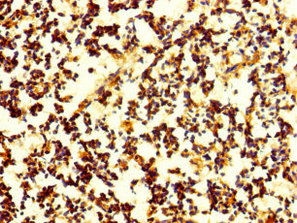

ApplicationELISA, IHC; Recommended dilution: IHC:1:20-1:200